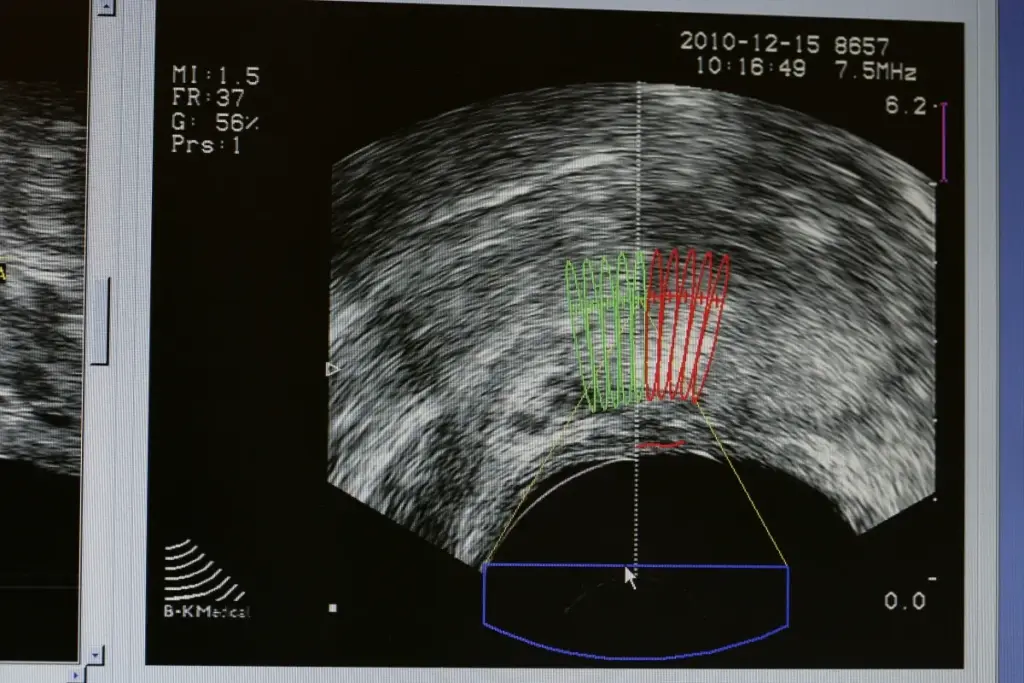

Doppler Ultrasound

Doppler ultrasound measures blood flow using the Doppler effect. It helps find testicular issues by looking at blood flow changes. It’s great for telling the difference between harmless and harmful growths.

Benefits of Doppler ultrasound include:

- Measurement of blood flow to detect abnormalities

- Ability to distinguish between benign and malignant growths

- Enhanced diagnostic accuracy when used alongside scrotal ultrasound

Vascularity |

Usually not increased |

Often shows increased vascularity on Doppler |